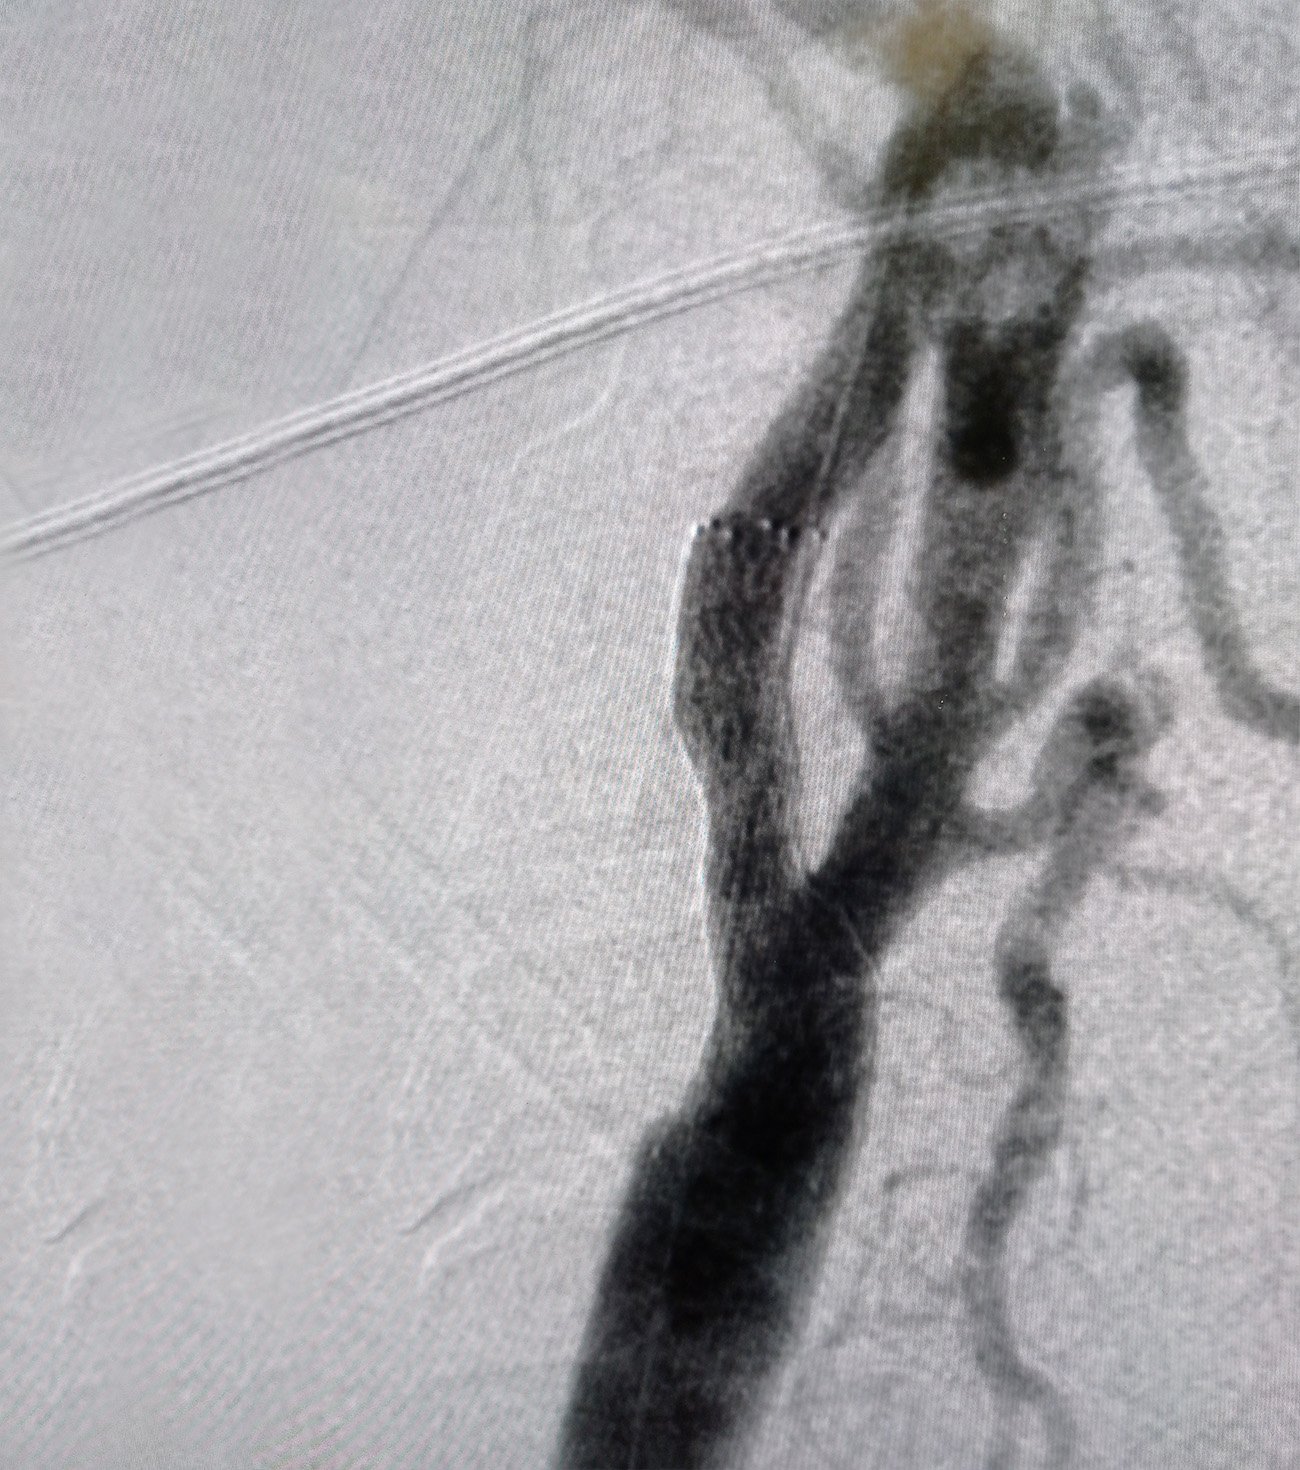

1. Τοποθέτηση καρωτιδικού stent (CAS):

• Ελάχιστα επεμβατική τεχνική με καθετήρα από τη μηριαία αρτηρία.

• Τοποθετείται ενδονάρθηκας (stent) που διατηρεί ανοιχτό τον αυλό της αρτηρίας.

• Επιλέγεται κυρίως σε ασθενείς υψηλού κινδύνου για χειρουργείο ή με ανατομικές δυσκολίες.